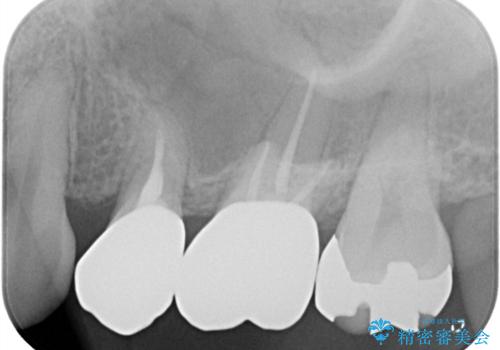

保険のメタルインレーは腐食しやすかったり、適合があまり良くなかったりで二次的にう蝕がインレー下で広がってしまうことが多々あります。

メタルインレーを除去したところ、残存歯質量が少なく破折のリスクを説明し、ゴールドクラウンでのやり替えとなりました。

保険のメタルインレーから二次う蝕予防(保険のメタルインレーは腐食しやすかったり、適合があまり良くなかったりで二次的にう蝕がインレー下で広がってしまうことが多々あります。)のためのやり替えだったため、材料としてセラミックとゴールドを提案したところ、展延性に優れ違和感の少ないゴールドを選択されました。